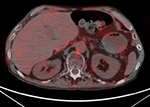

| 78 year-old man with lung cancer. FDG MIP image (A), PET-CT axial fused images at the level of tracheal bifurcation (B) and through the upper abdomen (C) demonstrate diffuse increased FDG uptake within the muscles with markedly decreased uptake within the brain, right hilar nodal mass, and within the liver. Comparison FDG PET (D, E, F) two weeks later following proper preparation shows intense uptake in the brain, with abnormal activity in the hilar nodes. Figure 25 (A-C) non-fasting state and Figure 25 (D-F) is fasting state. |

| 78 year-old man with lung cancer. FDG MIP image (A), PET-CT axial fused images at the level of tracheal bifurcation (B) and through the upper abdomen (C) demonstrate diffuse increased FDG uptake within the muscles with markedly decreased uptake within the brain, right hilar nodal mass, and within the liver. Comparison FDG PET (D, E, F) two weeks later following proper preparation shows the physiologic intense uptake in the brain, with abnormal activity in the hilar nodes. |